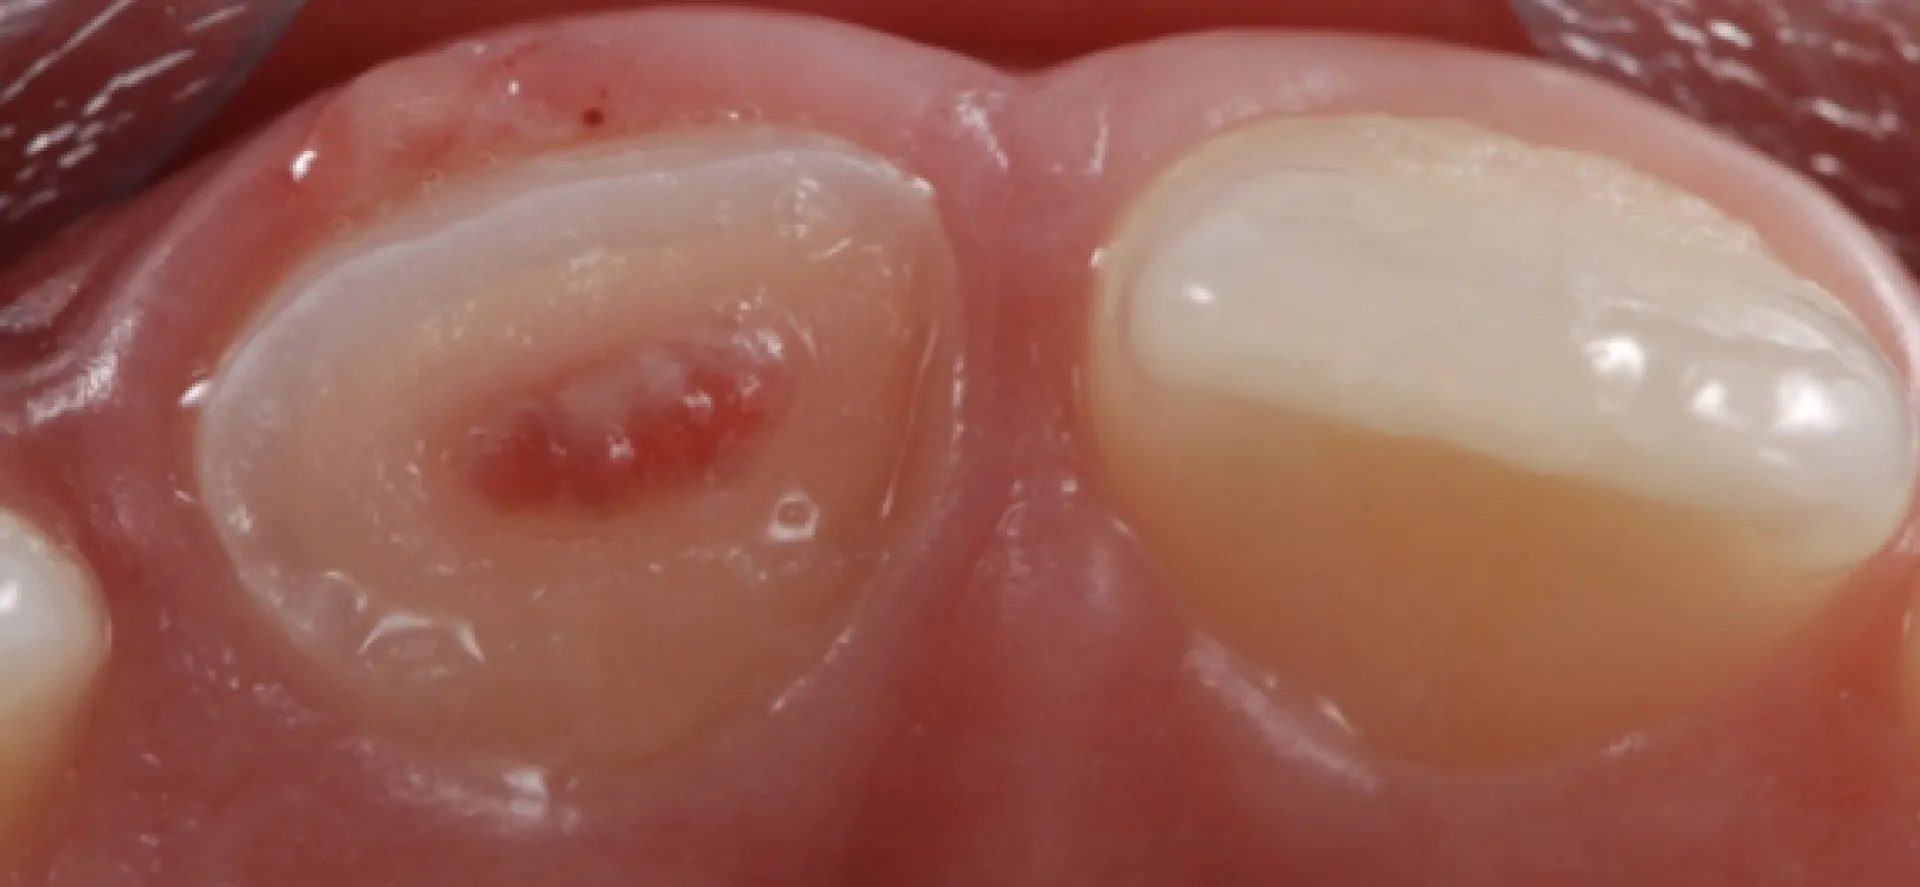

El present títol va dirigit a dentistes generals que busquin ampliar coneixements en el maneig de dents permanents joves, així com en l'ús de biomaterials en el tractament pulpar d'aquests.

• Aprofundir en el concepte i característiques de les dents permanents joves.

• Indagar sobre els factors etiològics més freqüents.

• Conèixer les claus d'un precís diagnòstic en dentició permanent jove.

• Conèixer la teràpia indicada en dents amb polpa vital.

• Conèixer la teràpia indicada en dents amb polpa no vital.

• Analitzar les característiques i maneig clínic dels biomaterials.

L'alumne serà capaç de diagnosticar i tractar dents permanents joves sota els criteris d'odontologia mínimament invasiva.